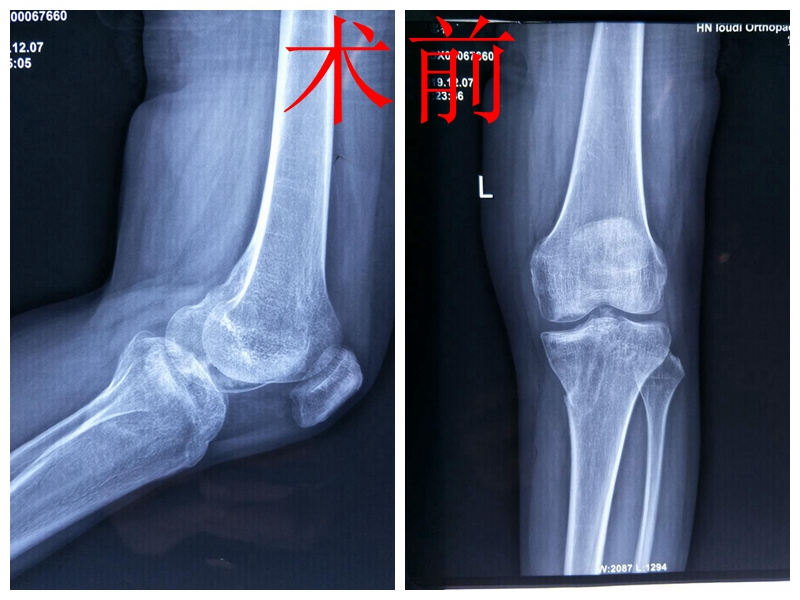

髋股膝胫科主任、副主任医师黄才平详细询问情况、仔细体格检查发现患者左膝部内翻畸形,左小腿外侧及左足背部无力抬起,完善相关检查后,诊断为左膝胫骨平台陈旧性骨折畸形愈合 、左膝关节内侧副韧带损伤。

膝关节是创伤性畸形最常见的部位,其主要原因之一是膝关节在本质上作为铰链发挥作用而缺少代偿作用,罗女士骨折畸形愈合原因为受伤后“水师”错误的处理方式所致。考虑其年纪不大,为打好“膝关节保卫战”,避免关节置换,黄主任邀请院长、大骨科专家刘卓华、髋股膝胫科首席专家刘文志、业务院长谢军、麻醉专家胡金英、隆清等进行专家大会诊,专家们一致认为截骨矫形手术是目前治疗罗女士胫骨平台畸形愈合的最有效方法。

罗女士十分后悔之前错误的治疗延误病情,希望尽早手术,脱离苦海。然而,胫骨平台骨折为关节内骨折,手术难度大,是创伤骨科中治疗的难点。该手术要求施术者具有丰富的临床经验,对截骨平面角度、高度、精确度要求甚高,一旦闪失,直接影响手术效果。